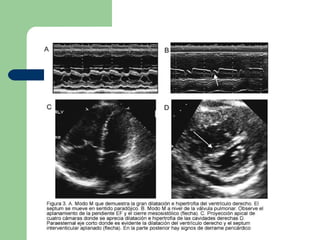

Ecocardiograma Util para demostrar hipertensión pulmonar y descartar patología estructural que cause la enfermedad. Para el diagnóstico de la hipertensión pulmonar, se deben tener en cuenta signos indirectos como: Dilatación e hipertrofia de las cavidades derechas Dilatación de la arteria pulmonar  Aplanamiento del tabique interventricular ( Figura 3 ).

Ecocardiograma Util parademostrar hipertensión pulmonar y descartar patología estructural que cause la enfermedad. Para el diagnóstico de la hipertensión pulmonar, se deben tener en cuenta signos indirectos como: Dilatación e hipertrofia de las cavidades derechas Dilatación de la arteria pulmonar Aplanamiento del tabique interventricular ( Figura 3 ).